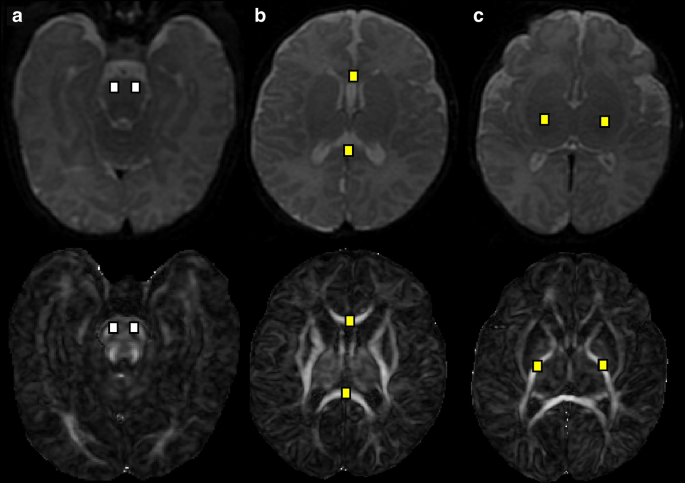

Volumetric segmentation was performed on coronal T2 Cube 3D images using a validated automated algorithm via the Draw-EM (Developing brain Region Annotation With Expectation-Maximization) package,40 with subsequent manual inspection and correction as needed by two investigators blinded to enteral nutrition type (KO and KK).37 Tissue-specific brain volumes were obtained for the cortical and deep gray matter, white matter, amygdala-hippocampus, cerebellum, and brainstem; total brain volume was calculated as the sum of all tissue-specific brain volumes for each infant (Fig. 1). DTI data were preprocessed based on a previously published pipeline, with cubic regions of interest (21-49mm3) manually placed by two investigators blinded to enteral nutrition type (KO and KK) using predefined anatomical landmarks in the corpus callosum (genu and splenium), posterior limb of internal capsule, and brainstem (pons).41 Fractional anisotropy (FA) and mean diffusivity (MD) values, measuring directionality and net diffusion of water molecules, respectively, were calculated for each region of interest. Inter- and intra-rater reliability measures for manually corrected MRI brain volumes and DTI region of interest placement were calculated based on a randomly selected subset of 35 patients using the intraclass correlation coefficient.

White matter microstructure

Term-equivalent DTI data were available for 146 (96%) infants (64 mother’s own milk, 43 donor human milk, 39 preterm formula); 6 were excluded due to poor DTI image quality. Intra- and inter-rater reliability intraclass correlation coefficients for ROI placement were 0.99 and 0.98, respectively. After adjusting for gestational age at birth and postmenstrual age at MRI, infants receiving donor human milk demonstrated lower MD in the brainstem (pons) compared to mother’s own milk (right: 0.78 ± 0.06 vs. 0.81 ± 0.08 mm2/second x10–3, β = –0.04, p = 0.008; left: 0.78 ± 0.07 vs. 0.82 ± 0.09 mm2/second x10–3, β = –0.06, p < 0.001) (Table 3) (Fig. 3a), with no significant differences between groups in FA (Table 4). A sensitivity analysis comparing infants who received >70% cumulative enteral nutrition from donor human milk (n = 17) to mother’s own milk (n = 62) also revealed lower MD in the brainstem (pons) of donor human milk-fed infants (right: β = –0.06, p = 0.018; left: β = –0.06, p 0.008).

Infants receiving preterm formula demonstrated higher MD compared to mother’s own milk in the corpus callosum (genu: 1.32 ± 0.18 vs. 1.22 ± 0.22 mm2/second x10–3, β = 0.11, p = 0.007; splenium: 1.28 ± 0.28 vs. 1.14 ± 0.22 mm2/second x10–3, β = 0.13, p = .007) (Fig. 3b) and posterior limb of internal capsule (right: 0.96 ± 0.1 vs. 0.91 ± 0.1 mm2/second x10–3, β = 0.06, p = 0.002; left: 0.97 ± 0.1 vs. 0.91 ± 0.1 mm2/second x10–3, β = 0.06, p = 0.001) (Fig. 3c), and lower FA in the right posterior limb of internal capsule (0.59 ± 0.06 vs. 0.62 ± 0.06, β = –0.02, p = 0.019). Adjusting for systemic steroid exposure attenuated this FA difference in the right posterior limb of internal capsule (β = 0.024, p = 0.025) with no significant effects on MD (Supplementary Tables S2 and S3). Incorporation of SVI and infant sex into multivariate models revealed no significant effects. In post-hoc analyses, preterm formula-fed infants demonstrated significantly lower MD than donor milk-fed infants in all regions of interest, with significantly lower FA in the brainstem (pons) (right: β = –0.04, p = 0.018, left: β = –0.04, p = 0.025) (Table 5).